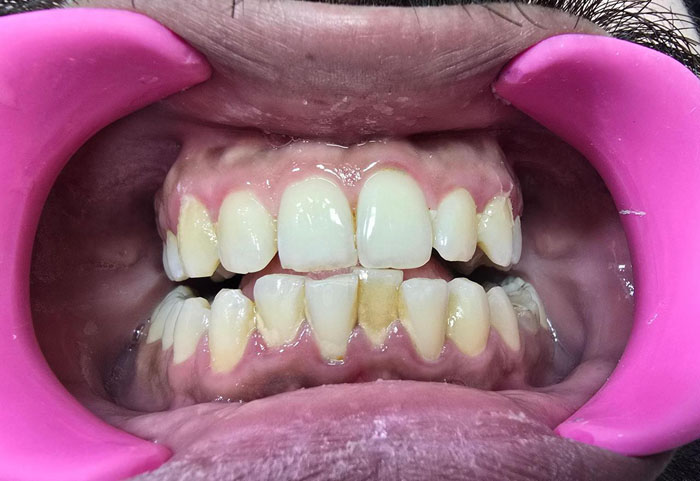

Every smile deserves gentle, thorough care—explore our EMS Guided Biofilm Therapy (GBT)

cases and see how patients leave with cleaner, healthier, and brighter smiles.

| Effectiveness | Removes deep-seated biofilm, improves gum health, reduces sensitivity, and enhances tooth brightness | Basic cleaning; less effective for deep biofilm and stubborn stains |